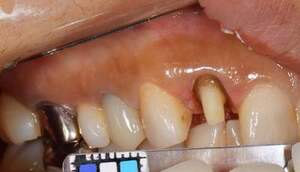

カリエス除去し、MTMを行ったのち、補綴を行う

全体的に10年以上前の治療痕で、銀歯の下でカリエスになっています。今回は右上5に限っての方針を記載する。 |

カリエスを取り除くと、遠心の歯質が歯肉縁下になりました。